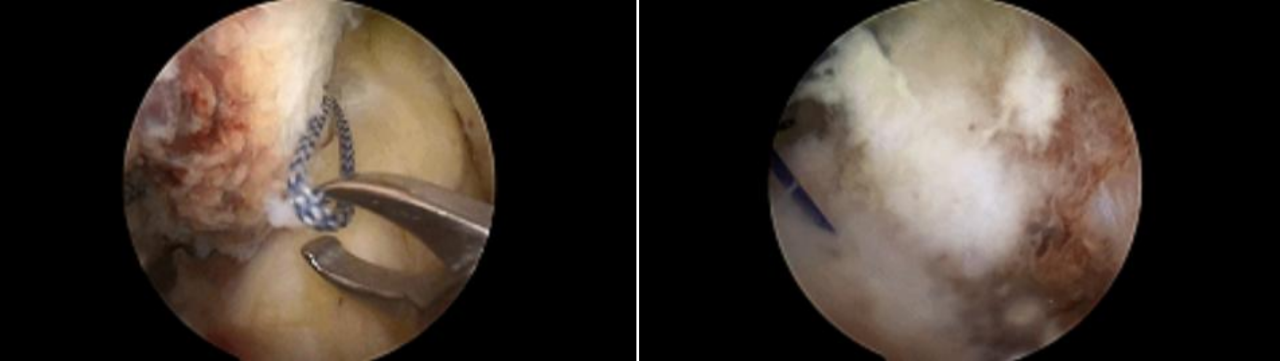

步骤1:暴露骨折段,插入定位器械,并构建一个直径为4.0mm的骨隧道。

步骤2:插入两条PDS线并引入高强线,分别并将其穿过后交叉韧带,以形成初始的吊带环。

第三步:双套环高强线复位骨折块,并穿入固定微孔钛板。

步骤4:将一根高强度缝合线穿过骨隧道,并牢牢收紧,以准确复位骨折段。

第五步:拉紧双环以稳定骨折部位,并抓住两条牵引缝线。

步骤6:紧固牵引缝线以防止固定环滑脱。